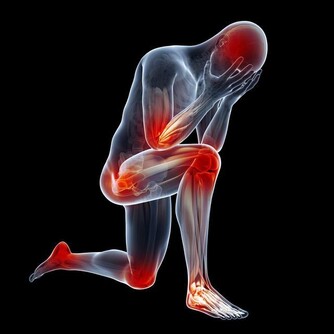

2、外界環境中的細菌易隨吸氣進入呼吸道及肺部。

(健康隱患:呼吸係統疾病)

遠離菸酒:在平日的生活中,煙、酒對於呼吸道的刺激,在AB型血的人中危害最大,所以要嚴格控製。

不宜吃過敏性食物:在所有血型中,AB型血的人患過敏性哮喘的比例最高,所以一切過敏性食物都要謹慎食用,比如魚、蝦、巧克力、羊肉等,以避免過敏性疾病的發生。